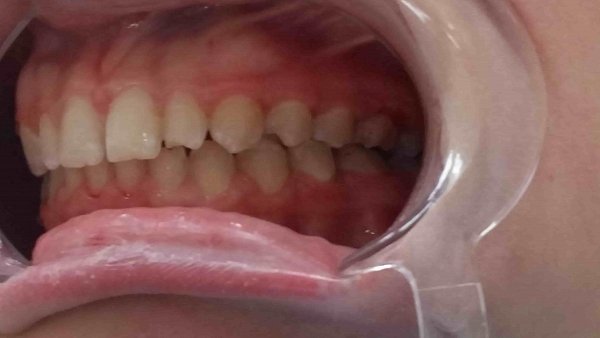

Пациентка 13 лет. Обратилась с жалобой на неправильный прикус.

Объективно: обратная резцовая окклюзия, вестибулярное положение зуба 2.3(клык) отсутствие зуба 1.2 (первичная адентия), сужение верхней челюсти, перекрёстная окклюзия справа, из анамнеза ротовое дыхание и аденоиды.

План лечение:

1)Расширение верхней челюсти с помощью аппарата РПЕ;

2)Удаление зубов мудрости нижней челюсти;

3)Лечение на брекет системе 2 челюсти с использованием техники многопетлевой дуги и ношениеэластических тяг.

4)Имплантация в области бокового резца после 18 лет

5)Лечение у ЛОРа.

Достигнуты результаты за 11 мсяцев:

1)расширение верхней челюсти

2)устранение обратного резцового перекрытия;

3)устранение скученности верхней челюсти;